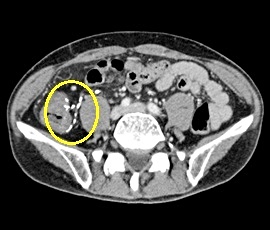

約6年前より繰り返す右側腹部痛と下痢を主訴にて精査目的に受診。腹部レントゲン検査にて、右側結腸の腸間膜側に一致した石灰化を認め、精査の結果、典型的な結腸辺縁静脈の石灰化と診断。手術(腹腔鏡下結腸切除術)を施行した。病理診断結果は、静脈硬化性大腸炎であった。

CT画像